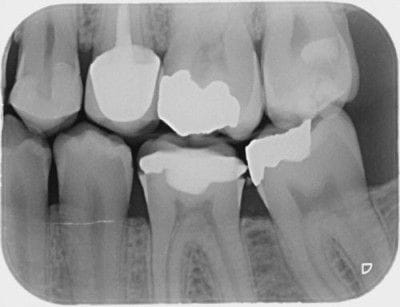

High-quality dental radiographs are essential for accurate diagnosis and treatment planning. They provide detailed, distortion-free images with optimal density and contrast. Achieving consistent quality requires team members to ensure proper positioning, exposure, and processing during image acquisition.

High quality dental radiography images are vital to both patients and clinicians, contributing directly to diagnosis and treatment planning. Quality radiographs feature maximum detail to resolve fine objects. The images accurately show the teeth and anatomic structure without distortion or magnification. They also exhibit density and contrast further improving a dentist's ability to diagnose and treatment plan. To ensure the dentist receives high quality radiographs every time, team members must focus on proper positioning, exposure, and processing during the acquisition process.